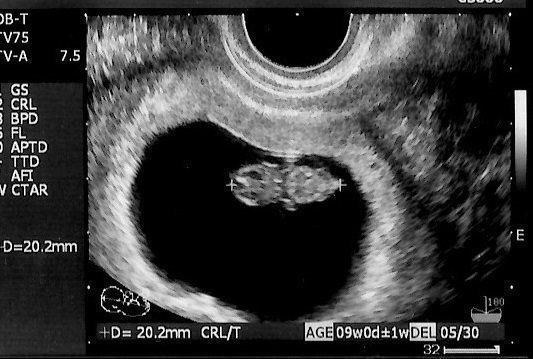

かえるさんの妊娠9週目のエコー写真

「もう、人の形をしている!」と驚きました。妊娠と同時に、里帰り先の産院を予約しました。その喜びをすべて吹っ飛ばしたのが、“つわり”。程度は違うものの皆さん経験するようですが、私は、家のビニール袋がすべてなくなるまで吐いてしまうという重症でした。内科で毎日点滴を受けながら乗り切り「母が食べられなくても、赤ちゃんて育つものだなぁ」と、感心しながら健診を受けていました。